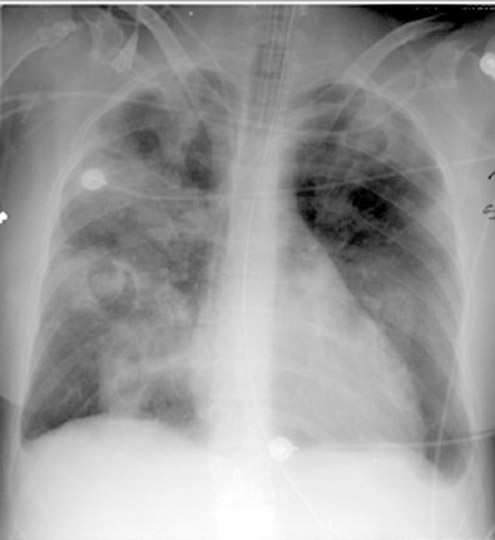

Case 2 Labeled Image What is the differential for multiple cavities?

Case 10 Labeled Image What is the differential for multiple cavities?